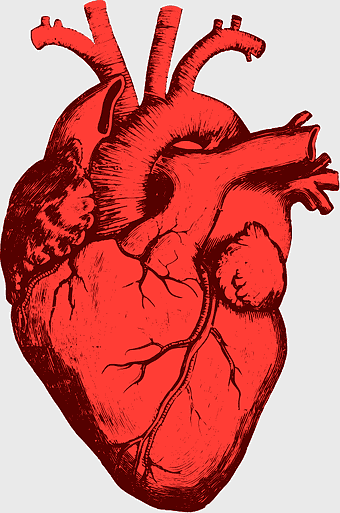

red heart anatomy, human heart drawing, cartoon heart illustration, love and biology, cardiovascular system diagram, medical art depiction, organ structure visualization -

Heart Anatomy Diagram, human heart drawing, realistic heart illustration, cardiovascular system, medical illustration, organ structure, human anatomy study -

human heart anatomy, cardiovascular system illustration, medical heart diagram, heart organ structure, human body organ visuals, anatomical heart drawing, heart health -

human heart anatomy, cardiac muscle illustration, circulatory system model, heart health visual, cardiovascular organ diagram, medical heart image, visceral structure depiction -